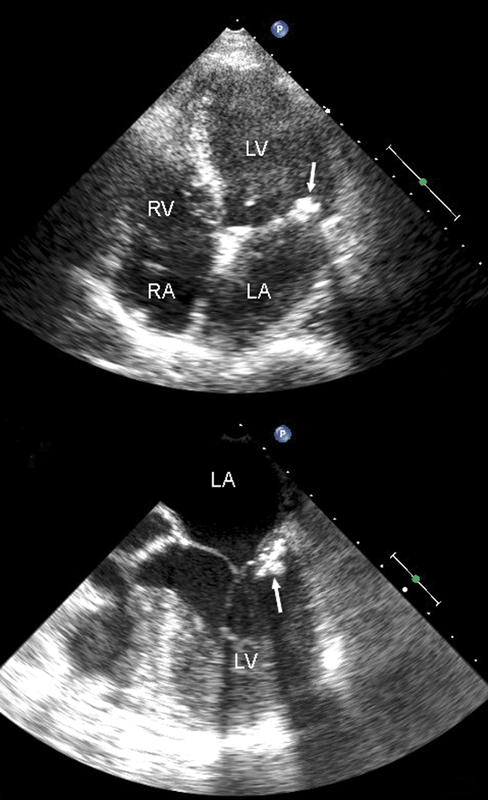

فحوصات تشخيصية لبعض امراض القلب والشرايين التاجية